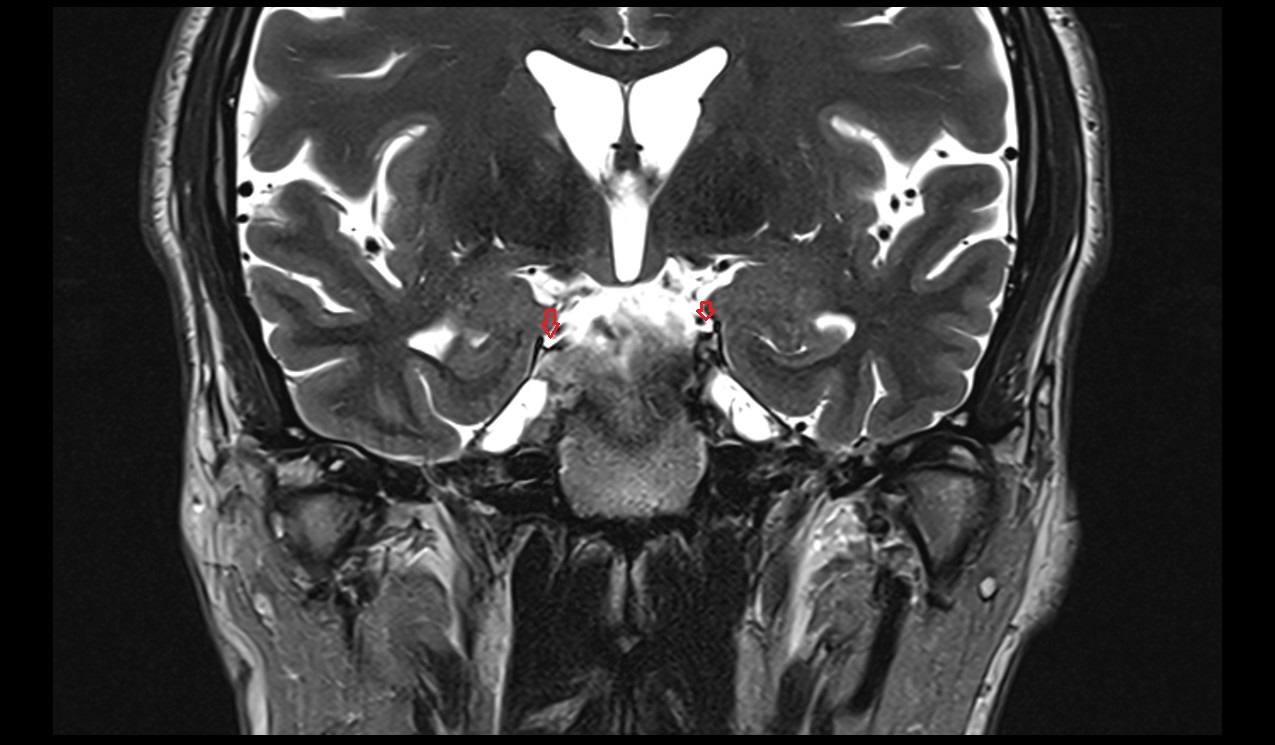

- Hippocampus